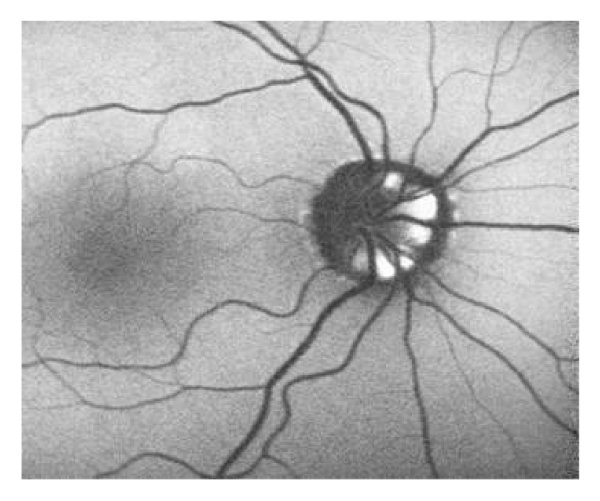

A 46-year-old man was examined by us for minor ocular problems in January 2009. He had received a diagnosis of type 2 diabetes mellitus five years priorly and has been known to have congenital color blindness. At that time, his best-corrected visual acuity (BCVA) with Snellen chart was 8/10 in OD and 7/10 in OS. Slit-lamp examination was normal OU. Fundus examination and autofluorescent imaging showed bilateral mild nonproliferative diabetic retinopathy and optic disc drusen (Figures 1(a), 1(b), 1(c), and 1(d)).

(a)

(b)

(c)

(d)